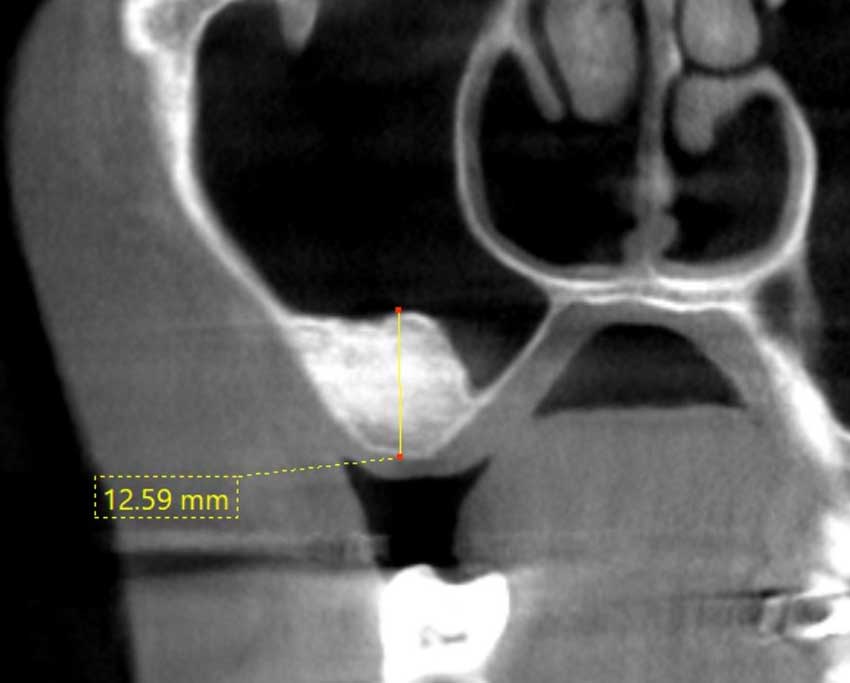

治療前

サイナスリフト GBR

インプラントを埋入する骨の厚みが十分にありません。

治療後

人工の骨を使って骨の厚みを確保し、インプラント治療を行いました。